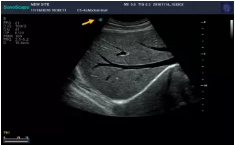

(1)滑:整個超聲探頭平面緊貼受檢區(qū)域皮膚,沿著一定方向滑行。

(2)搖:整個超聲探頭平面緊貼受檢區(qū)域皮膚,以超聲探頭與胸壁的接觸點為支點,將超聲探頭左右搖擺,觀察整個切面。

(3)傾:整個超聲探頭平面緊貼受檢區(qū)域皮膚,以超聲探頭與胸壁的接觸點為支點,將超聲探頭前后傾斜,觀察不同切面。

(4)轉(zhuǎn):整個超聲探頭平面緊貼受檢區(qū)域皮膚,以超聲探頭與胸壁的接觸點為支點,超聲探頭以自身中軸線順時針或逆時針方向旋轉(zhuǎn)一定角度。